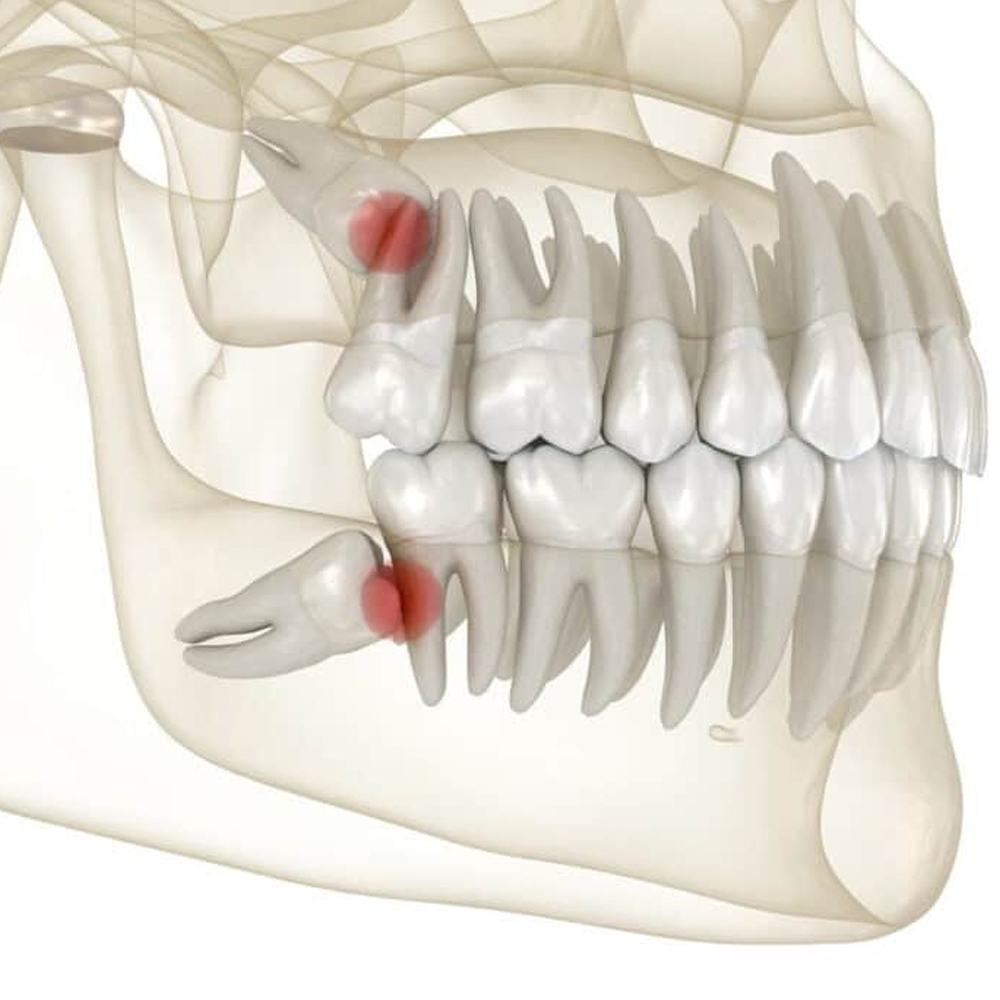

Periodontal hastalıklar, toplumda çocukluktan yaşlılığa kadar her yaşta insanı farklı şiddette etkileyebilmektedir. Çoğu zaman hastanın ağrı gibi bir şikayeti olmadığı için belirti vermeden ilerleyebilmektedir. Hastanın şikayeti olduğunda ise sağlam ve çürüksüz dişler, destek dokulardaki kayıplardan dolayı sallanarak kaybedilmektedir.

Periodontitis; diş ve dişi destekleyen dokuların (periodontal ligament, sement, alveol kemiği) yıkımıyla karakterize iltihapsal bir hastalıktır. Diş eti iltihabı, alveol kemiğine (çene kemiği) kadar ilerlemiştir. Periodontitisin temel nedeni; bakteri plağıdır ve mekanik olarak tedavi edilebilir. Ancak genetik, çevresel ve sistematik faktörler de hastalığın oluşmasında etken olabilir. Sistemik faktörler içinde diabet, kalp damar hastalıkları, epilepsi, down sendromu, AIDS ve kan hastalıkları sayılabilir.

Periodontal tedavinin ana amacı ise umutsuz gibi görünen sağlıksız dişleri ağızda tutmaktır. Hastalığın tipi ve şiddetine göre değişik tedavi yöntemleri uygulanabilir. Bunlar; öncelikle ağız hijyeni eğitimi, diş taşı temizliği, kök yüzeyi düzleştirilmesi, rejeneratif, rekonstrüktif ve mukogingival operasyonlar olarak özetlenebilir. Aynı zamanda yüksek gülme hattı olan bireylerin diş eti estetiğini sağlamak da, periodontal tedavi kapsamındadır. Hastalığın tipi ve şiddeti, hastanın alışkanlıkları, hekimi ile yapacağı işbirliği, ağız hijyeninin standardı, tedavi planlaması ve başarısını doğrudan etkiler.